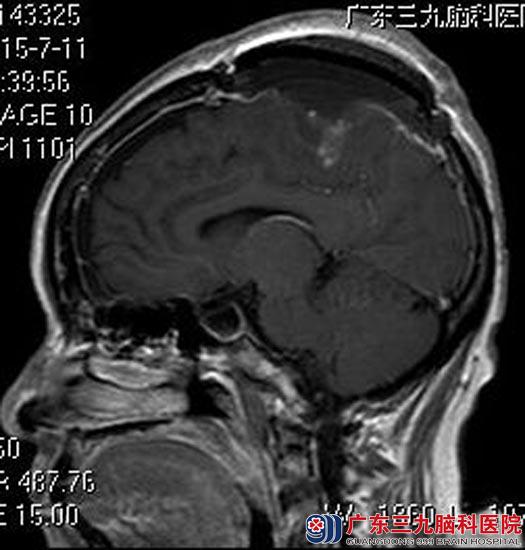

完善术前检查后,由鲁明主任主刀,在全麻下行双侧额顶部镰窦旁脑膜瘤切除术+颅骨修补术,术中显微镜下见肿瘤质韧,分块予以全切除,手术顺利。现红大姐已康复出院,术后病理回报:过渡型脑膜瘤(WHO I级)。

▲手术后